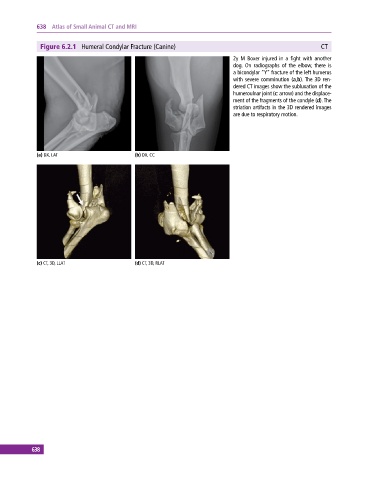

Figure 6.2.1 Humeral Condylar Fracture (Canine) CT

2y M Boxer injured in a fight with another

dog. On radiographs of the elbow, there is

a bicondylar “Y” fracture of the left humerus

with severe comminution (a,b). The 3D ren-

dered CT images show the subluxation of the

humeroulnar joint (c: arrow) and the displace-

ment of the fragments of the condyle (d). The

striation artifacts in the 3D rendered images

are due to respiratory motion.

(a) DX, LAT (b) DX, CC

(c) CT, 3D, LLAT (d) CT, 3D, RLAT